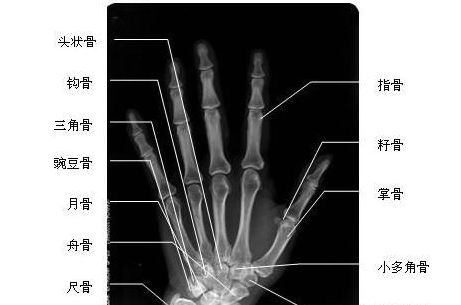

手正位-X线图

手正位-X线